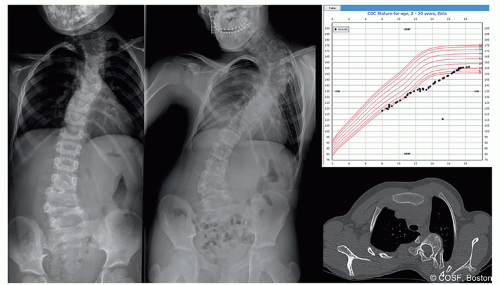

(Figure 1.1). The Risser classification and state of the triradiate cartilage are the most commonly used markers for growth, but the Risser sign in particular can be misleading. The Sanders digital score helps with assessing stage of growth in healthy early and late adolescents. For more complex situations and younger children, bone age determination can help greatly in assessing the stage in growth. The pediatric growth chart on paper or in the electronic medical record offers additional insight into the complex patient. Failure to grow, poor nutrition, and stage in growth are most sensitively displayed in the growth chart; much more than the snapshot in time that a single-hand x-ray displays. Knowledge of stage in growth, height percentile, and access to the growth chart allows a reasonable estimate of predicted final height. Spinal curvature, multiple congenital vertebral anomalies, and spinal fusion all negatively impact spine length. Assessing the potential effect of treatment on spine height is integral to deciding on treatment. A working knowledge of Dimeglio or others’ data on spinal growth is essential to making treatment choices. Actually calculating the predicted growth remaining and discussing with family facilitates a correct choice.

The rate and timing of progression vary widely in pediatric spine deformity with differing diagnoses and ages. Accurately predicting the future of a deformity with a particular diagnosis is challenging, but made more likely by a thorough knowledge of the natural history of that particular diagnosis. For example, spontaneous improvement is likely in infantile idiopathic scoliosis (IIS) with a low rib-vertebral angle difference (RVAD) or in developmental thoracolumbar kyphosis (Figure 1.2), while progression of a dysplastic kyphoscoliosis in neurofibromatosis in the preadolescent growth spurt is inevitable. Many congenital deformities progress during rapid growth in the first 3 years of life, remain stable through the remainder of childhood, and then progress again with the early adolescent growth spurt (Figure 1.1). Knowledge of these diagnosis-specific natural histories permits accurate timing of intervention and avoids unnecessary treatment. Deformity behavior after growth is similarly dependent upon underlying diagnosis. Localized congenital deformity within the thorax likely remains stable after growth in spite of a large Cobb angle, while a thoracolumbar curve with a lesser magnitude in a connective tissue disorder will steadily progress after growth. Neuromuscular patients with poor core muscle strength may likewise progress steadily after maturity. Measuring deformity Cobb angle is an incomplete predictor in pediatric spine deformity. Only by knowing the natural history of the individual diagnosis can we make appropriate surgical choices.